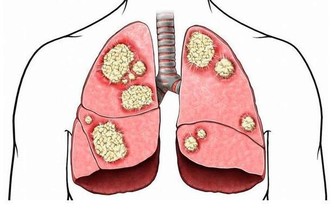

而且由於長期未治好,終於把食道燒傷,結果就是食道癌、胃癌或淋巴癌或胰臟癌。

還會引起鋁中毒,產生腦神經損壞,甚至與柏金生氏症有關,副作用不勝枚舉。